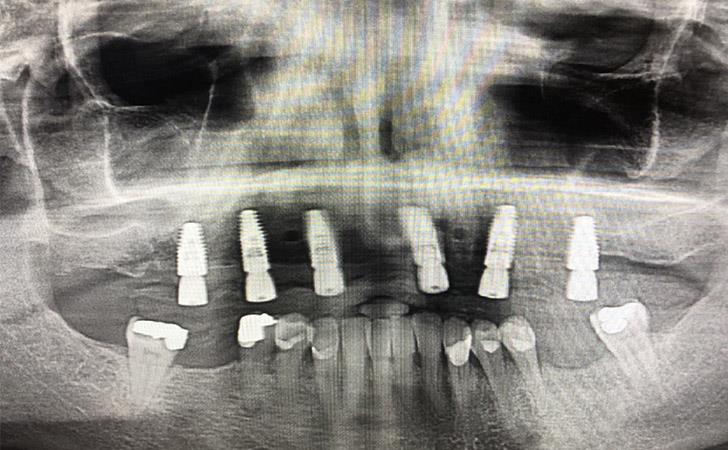

59 year old male who wore an upper full denture for over 20 years wanted to convert his situation to a non removable implant supported restoration. Using guided implant surgery and planning, nSequence, I was able to plan the precise position of his implants and place them using a surgical guide. The restorative dentist then placed his teeth attached to his newly placed implants the same day - a total makeover!!